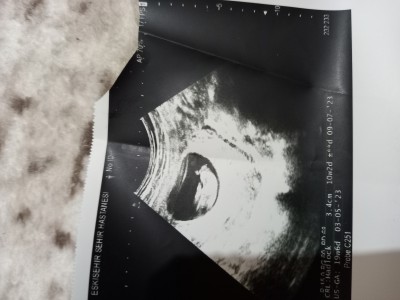

Elimde olan bütün ultrasyon fotoğrafları bunlar

21.hafta ayrıntılı ultrasyona girdim 10 dk sürdü sürmedi bebek çok hareketli görüntü yakalayamiyorum ama kiz dedi 21.haftanin ultrasyon fotoğrafını da vermedi elime

En sondaki fotoğrafta ok işaretiyle bile göstermiş erkek işte bariz belli daha ne diyelim ne istiyorsun hayırlı olsun aynı şeyi sormaktan bıkmadın mı ☺

Kızların klitoristi daha önce gelisiyormuş. Yan dudaklarda şişkinlik oluyormuş bu yüzden kız bebekleri bazen erkek zannedebiliyorlarmis doktorlarinda ayrıntılı olmadan kesin söylemesi zor olabiliyor. Şuan dikkatli bakarsan iki tarafta şiş olan yan dudakları var. ortadaki çıkıntı zamanla normal boyutuna döner. Affesedersiniz ama bu kadar ufacık bir bebeğin hayalarının bu denli büyük olması biraz tuhaf olmaz mıydı?

You tobe a KAĞAN KOCATEPE KİZ BEBEKLER neden erkek gibi görünür yaz canım bak orda açıklama yapıyor. İç dudaklar ve dış dudaklar şiş klitorist büyük olduğu için erkek gibi görünebiliyormuş.

Ayrıntılı ultrason dediyse doğrudur

Hem cinsiyet değişmez sadece yanılma payı olur

Sana prenses gelicek gözün aydın

Son fotoda gostermis zaten kiz canim o kac haftaliksa artik nettir